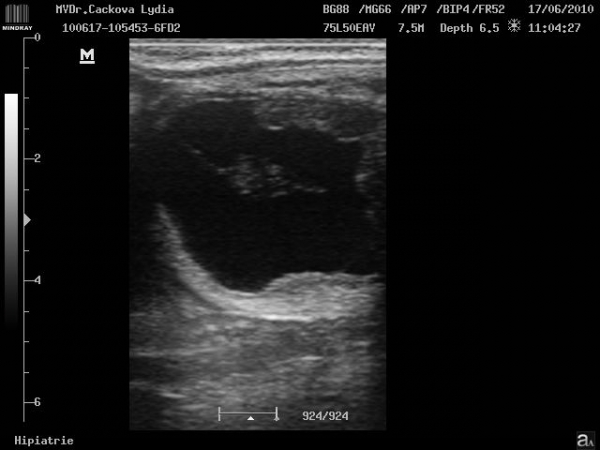

Embryo 31. den